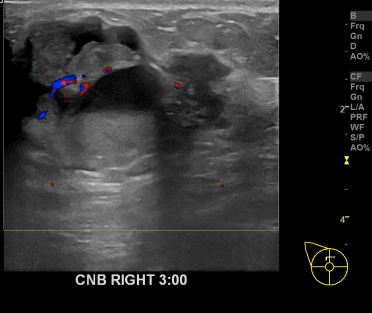

아산유외과개원후 653번째 유방암진단

상기환자 외부검사상 이상소견으로 내원하신 60대여성으로 우측유방의 의심스러혹

조직검사시행해 유방암 진단되었습니다.